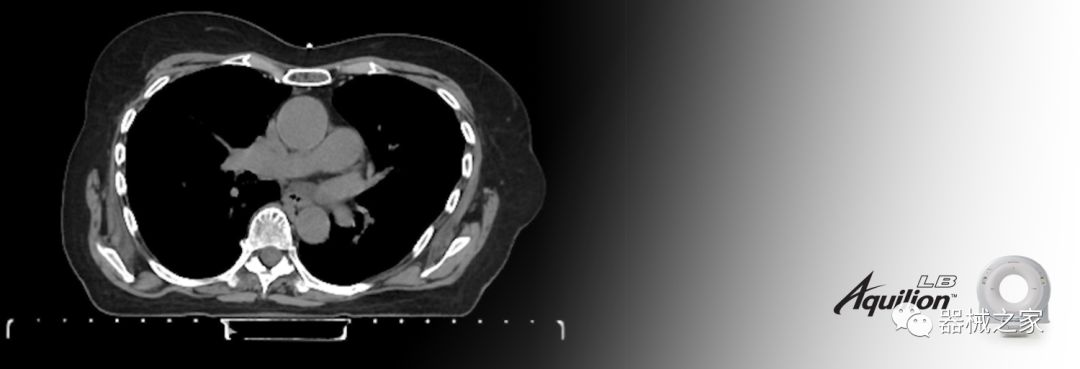

在以患者為中心的放射腫瘤學領(lǐng)域,計算機斷層掃描(CT)的可訪問性,可重復(fù)性和靈活性至關(guān)重要。為了建立這些價值,佳能醫(yī)療系統(tǒng)美國公司現(xiàn)在正在擴大其放射腫瘤學CT模擬產(chǎn)品,包括Aquilion Prime SP和Aquilion Lightning 80高級CT系統(tǒng)。除了Aquilion LB之外,Aquilion Prime SP和Aquilion Lightning 80現(xiàn)在還包括放射治療(RT)選項,可為腫瘤學規(guī)劃提供高質(zhì)量的CT成像和精密工具。

Aquilion LB專為滿足腫瘤學挑戰(zhàn)而設(shè)計,同時優(yōu)先考慮患者護理。Aquilion LB的內(nèi)徑為90 cm,能夠幫助復(fù)雜的患者設(shè)置并提高患者的舒適度。CT模擬定位可以輕松鏡像放射治療定位,更加自信。該系統(tǒng)采用0.5 mm x 16排(32層)PUREViSION探測器技術(shù),70 cm視野,AIDR 3D和SEMAR技術(shù)。